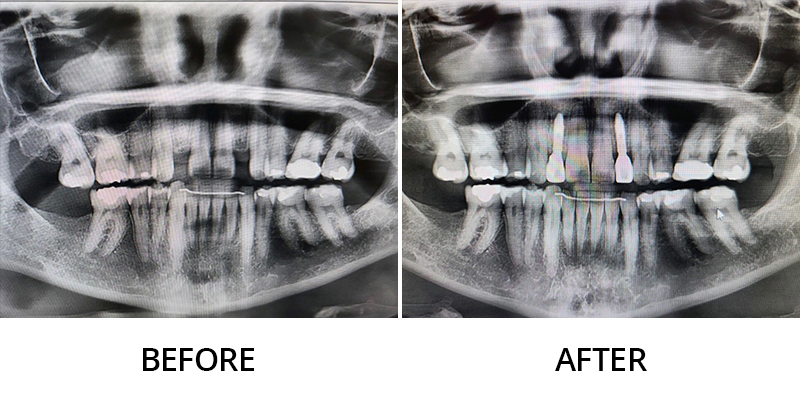

We invite you to explore this smile gallery page to see some of the beautiful results Dr. Kevin Grimm has helped his patients achieve. If you have questions about our dental services, or to schedule your personal consultation with our skilled dentist in Okemos, Michigan, please contact Okemos Smile Center today at 517-349-3110. We look forward to helping you transform your smile!